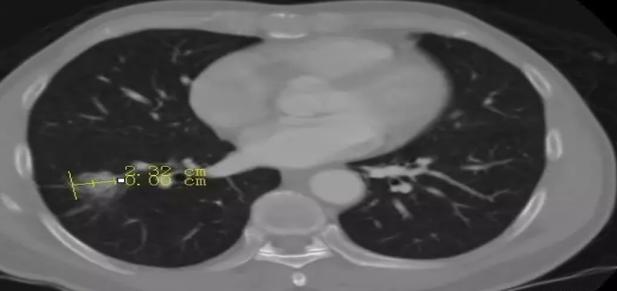

③咳嗽、血痰 不明原因的咳嗽、痰中带血,经治疗症状无明显好转或经常复发,若伴有咽痛,应是肺癌的早期信号。

CT扫描示右肺结节病变